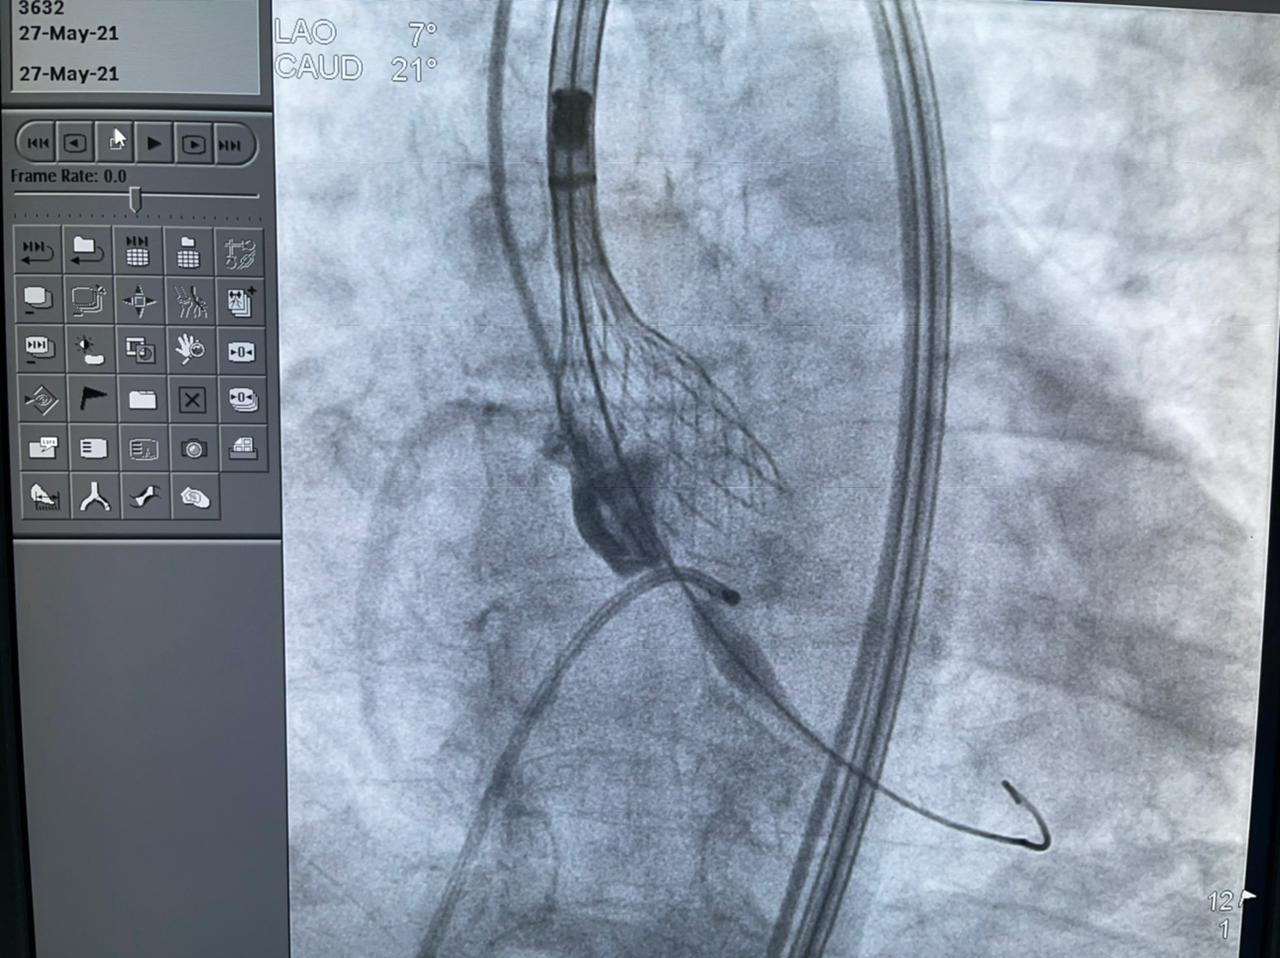

وأشارت الهيئة إلى أن الحالة الأولى من العمليات الدقيقة والمتطورة التي أجرتها مستشفى النصر التخصصي، كانت لمريض يبلغ من العمر 65 عامًا يعاني من ضيق شديد متكلس بالشريان التاجي الأيمن، بعد أن أجريت له جراحة قلب مفتوح منذ 15 سنة، وتم استخدام الشنيور الطبي لتوسيع الضيق، وتمت العملية بنجاح بالرغم من الصعوبة البالغة للحالة.

وأضافت الهيئة أن الحالة الثانية هي عملية زراعة الصمام الأورطي لمسنة تبلغ من العمر 78 عامًا، كانت تعاني من ضيق شديد بالصمام الأورطي، وتمت العملية بنجاح بعد أن كانت تعاني من تعب شديد وضيق بالتنفس وآلام بالصدر ونوبات إغماء، وتم إقرار علاج المريضة بعملية زراعة الصمام نظرًا لتقدم عمرها والضعف العام لحالتها الصحية، وتم إجراء العملية بتقنية التافي العالمية التي يتم بها تغيير الصمام الأورطي عن طريق القسطرة.

واستكملت أن الحالة الثالثة لمريضة تبلغ من العمر 70 عامًا، تعاني من قصور شديد بالشرايين التاجية للقلب وانسداد تام مزمن بالشريان التاجي الأيمن، إضافة إلى انسداد مزمن بالشريان التاجي الدائري الملنف وضيق شديد بالشريان الأمامي، ولها بنت مريضة من ذوي القدرات الخاصة، ولا تستطيع التغيب عنها لفترة طويلة، فتم علاجها على وجه السرعة عن طريق توسيع للشرايين بالبالونات العادية والدوائية إلى جانب تركيب دعامات دوائية لها باستخدام أحدث التقنيات العالمية بنجاح، واستطاعت الخروج من المستشفى في أقل من 24 ساعة لتعود إلى بيتها وابنتها التي تحتاج إلى رعايتها.

وتابعت الهيئة أنه قام بإجراء العمليات للمرضى الثلاثة في يوم واحد، فريق من أمهر الأطباء الأخصائيين والاستشاريين في علاج أمراض القلب والقساطر القلبية، يضم، الدكتور طارق رشيد أستاذ القلب والقسطرة وخبير حالات الانسداد المزمن للشرايين التاجية ورئيس قسم القسطرة القلبية بمستشفى النصر التخصصي، والدكتور ياسر صادق استشاري القلب وخبير القسطرة القلبية، الدكتور أمير البسطويسي استشاري جراحة القلب والصدر، الدكتور أحمد شبل استشاري القلب والقساطر التداخلية، الدكتور محمد علم الدين استشاري القلب والقسطرة العلاجية، الدكتور محمد لبيب استشاري جراحة الأوعية الدموية، وإخصائي علاج أمراض القلب والأوعية الدموية الدكتور معتز سلامة و الدكتور محمد عطا، أخصائي علاج أمراض القلب والقسطرة العلاجية الدكتور مصطفى رفعت، الدكتور أحمد عبد الرؤوف أخصائي التخدير بالمستشفى.